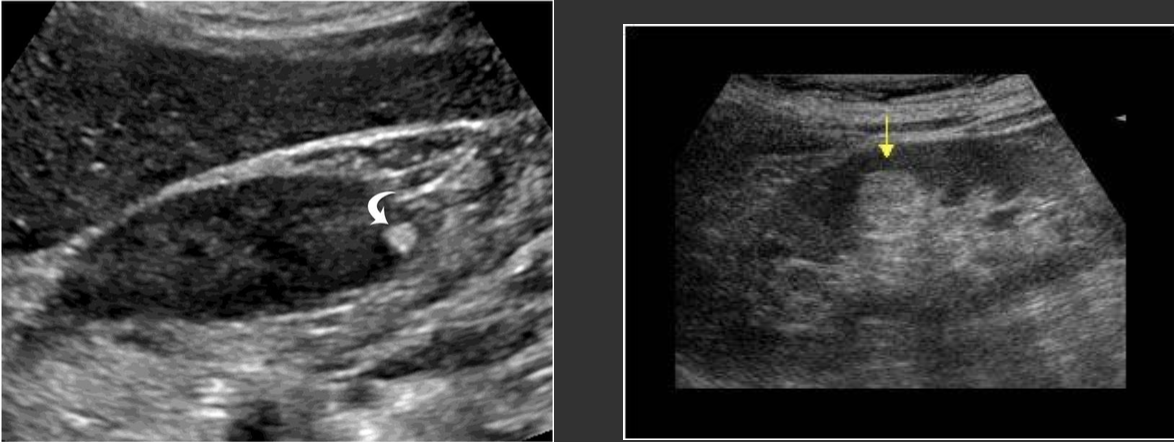

Nephrolithiasis → very common, calculi

2D US: echogenic foci, rounded surface, posterior shadowing

color doppler: twinkle artifact

DDX: milk of calcium cyst (location differs)